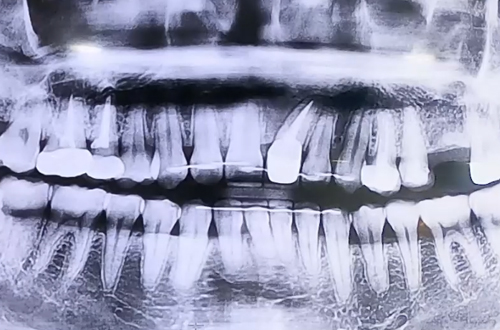

AFTER

치료 유형 어금니 임플란트, 앞니 충치 치료

치아는 그대로 살리면서 안쪽 충치를 치료한 뒤 염증을 깨끗이 긁어내고 잇몸을 닫는 치주 수술을 진행해드리며 임플란트 역시 함께 마무리 해 드렸던 케이스입니다.